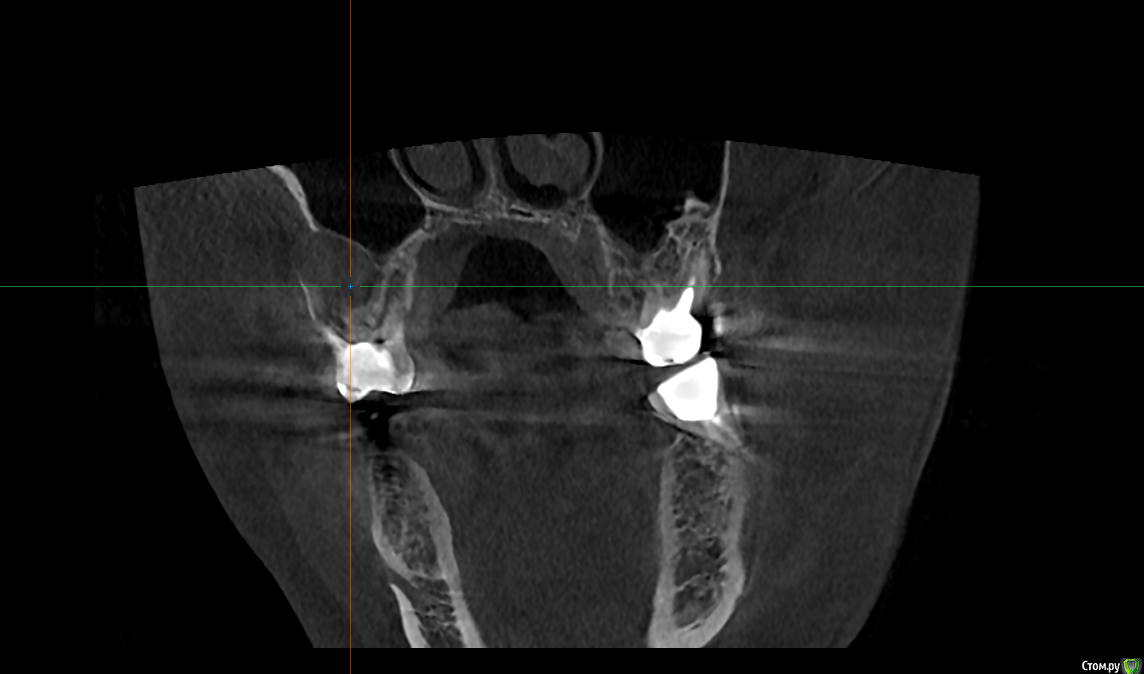

Raystom Опубликовано 20 февраля, 2021 Поделиться Опубликовано 20 февраля, 2021 Обратилась пациентка с неприятными ощущениями в области зубов 26, 27, во рту эти зубы показались мне темнее остальных, на КТ видна вот такая красота. Каков план лечения в таких ситуациях? Попробовать отделить пазуху от грануляций или просто удалить и после лечения ЛОРа идти на закрытие ОАС? Как после восстанавливать кость? И какие временные промежутки. Понимаю, что многие скажут при таких вопросах передать другим, но это не мой вариант. Мб есть литература по подобным случаям? Ссылка на комментарий

It'sGeorgy Опубликовано 20 февраля, 2021 Поделиться Опубликовано 20 февраля, 2021 А что именно смущает? Что дефект с пазухой сообщается? Так закроете после удаления, ничего страшного. ЛОРу, имхо, там делать нечего пока еще.Недавно был подобный случай: А вообще, судя по тем скринам, которые вы выложили, я бы пациента терапевтам показал для начала. Ссылка на комментарий

Raystom Опубликовано 20 февраля, 2021 Автор Поделиться Опубликовано 20 февраля, 2021 А что именно смущает? Что дефект с пазухой сообщается? Так закроете после удаления, ничего страшного. ЛОРу, имхо, там делать нечего пока еще.Недавно был подобный случай:12.png23.png22.png А вообще, судя по тем скринам, которые вы выложили, я бы пациента терапевтам показал для начала.Именно, что с пазухой. С терапевтами общались, при попытке препарирования зуб "мягкий", как кариозный судя по их словам Ссылка на комментарий